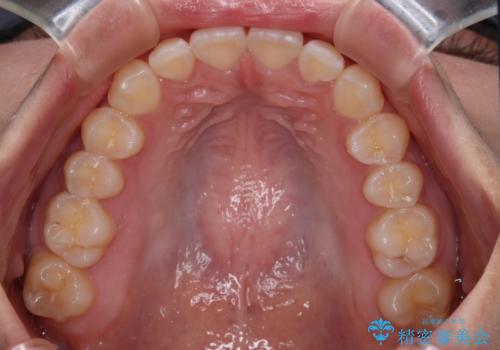

1年弱の短期間で、望み通りのスッキリとした口元に仕上げることができました。

デコボコをワイヤー装置で改善 短期間で綺麗な仕上がりに